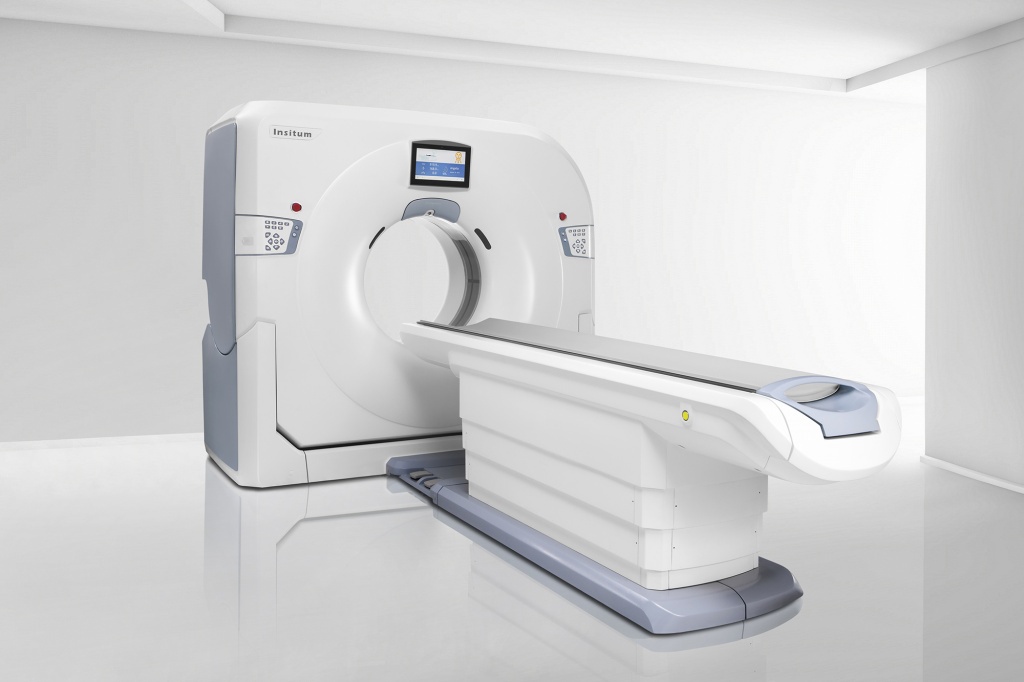

Серия КТ Insitum 32/64S/64

- Высокое разрешение

- Большая апертура (76 см)

- Быстрая работа (скорость вращения – 0,7 сек.)

- Позиционирование пациента одной кнопкой для быстрой работы

- Функция DFS – автоматическое изменение фокуса в реальном времени при обнаружении артефактов

Подходят для решения сложных задач общей диагностики, хирургии, сосудистой визуализации, моделирования и биопсии при онкологии.

Программное обеспечение на базе ИИ позволяет проводить постобработку с использованием облачных хранилищ и технологий удалённой диагностики, оценку морфологии, качественный анализ с помощью технологии спектральной визуализации.